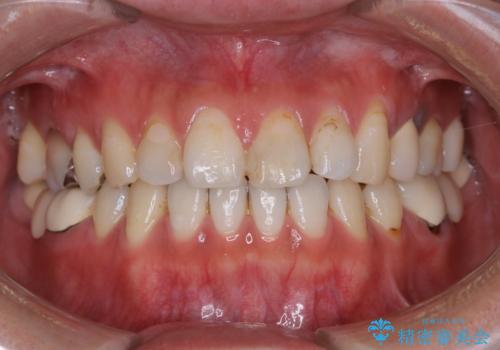

- 虫歯治療を始める前に、まずはしっかり汚れを取りたいとのことで来院されました。歯石やステインが分厚く付着していたため、PMTC60分コースを行いました。

歯の表面に、茶色く色が残っている所がありますが、これは詰め物の変色によるものです。以前に、CR(コンポジットレジン)による虫歯治療がされています。

CRは経年的劣化や、着色してしまうことがあります。PMTCでクリーニングを行うと、古いCRが目立つことがあるため、気になる際は詰め替えを行います。

茶色くなっている部分が、着色なのか、劣化なのか、虫歯によるものなのかは判別が難しいことがあります。そのため、定期的にPMTCを行うことで状態の確認が的確に行えます。